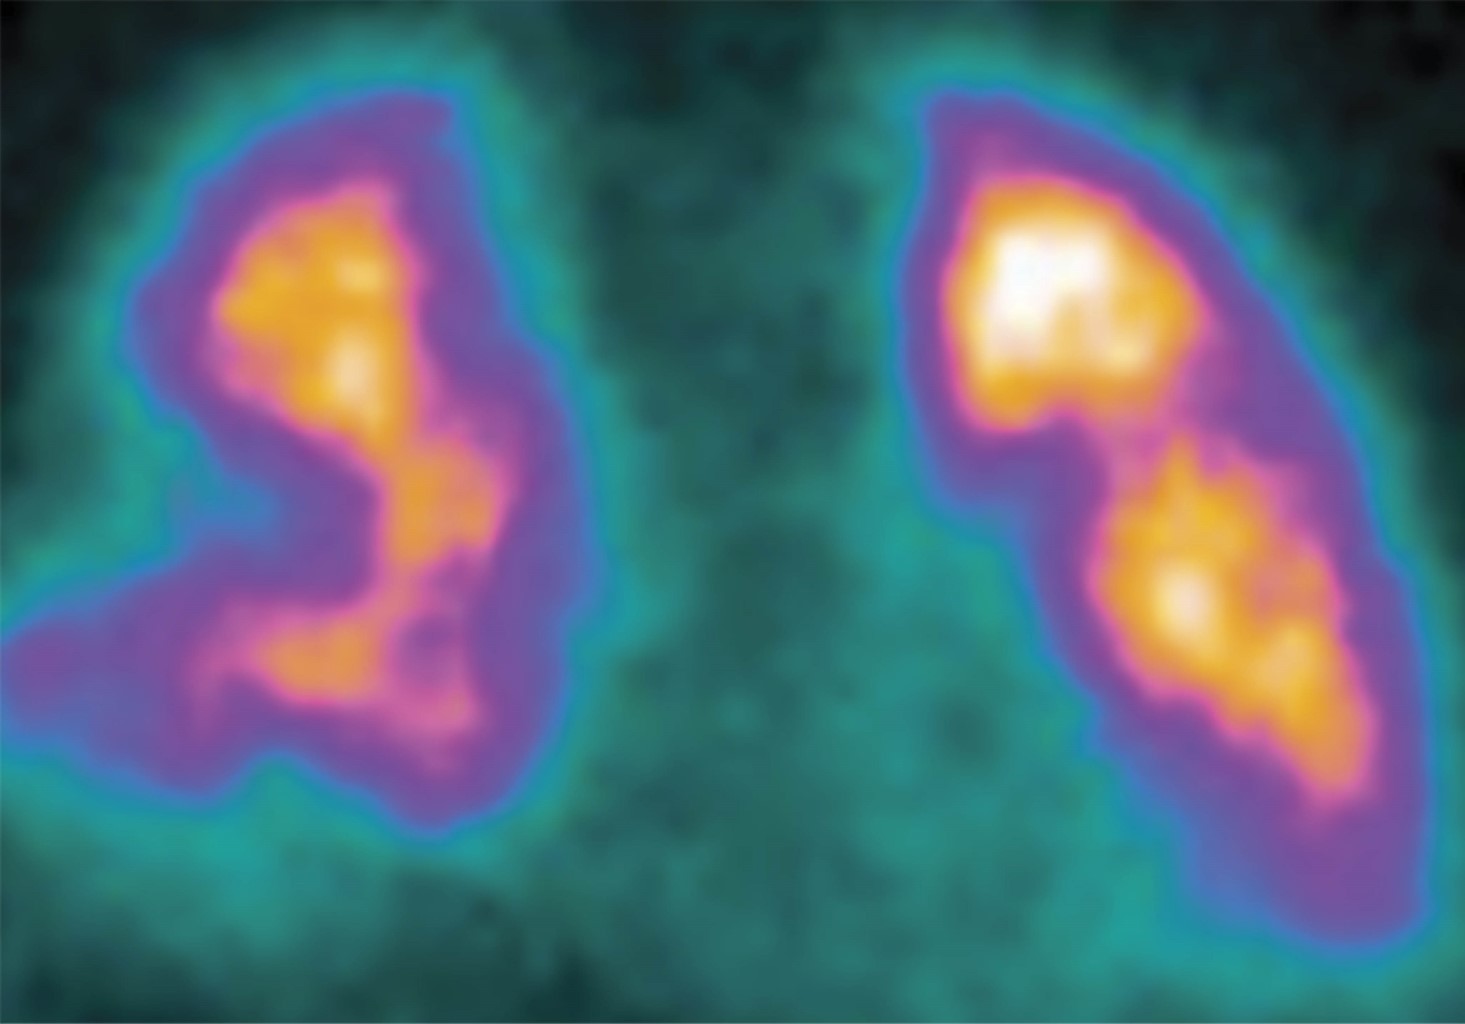

Paciente de 19 años de edad quien sufre accidente de tránsito en calidad de conductor de motocicleta por colisión contra una tractomula, lo que le ocasiona fractura diafisaria de fémur tibia y peroné en extremidad inferior derecha; se descarta etilismo en el sitio del accidente. Es llevado a centro de referencia donde presenta deterioro de la oxigenación por lo que requiere atención en Unidad de Cuidados Intensivos (UCI). Sin antecedentes de importancia familiares o personales, ingresa a UCI con índices de oxigenación alterados saturando 85% con mascara de no reinhalación, frecuencia respiratoria de 38 por minuto, frecuencia cardiaca de 100 por minuto, tensión arterial 90/55 mmHg, sin deterioro neurológico, Glasgow 15/15, temperatura de 38.5 oC. Al examen físico se documentan ruidos cardiacos taquicárdicos, ruidos respiratorios con crépitos bibasales y hematoma en región proximal del muslo con deformidad en tercio distal y exposición de material óseo. Se plantea la impresión diagnóstica de insuficiencia respiratoria aguda, embolismo graso y politraumatismo con múltiples fracturas en extremidad inferior derecha. Se realiza inducción de secuencia rápida con sedación analgesia y relajación, laringoscopía directa, Cormack-Lehane IV; se avanza tubo orotraqueal 7 con guía, previa BURP, sin registrar eventualidades.4,5 Mecánica ventilatoria seriamente afectada con distensibilidad estática de 18 cm, dinámica de 13 cm, presión meseta de 25 cm con presión de conducción de 18 cm y lesión pulmonar severa con PaO2/FiO2 de 85, por lo que se inicia protección pulmonar y titulación de presión positiva al final de espiración (PEEP) por bucle cuasiestático de presión y de volumen a partir de puntos de inflexión direccionado por EXPRESS.6,7 Se avanza línea central subclavia derecha, documentándose perfil distributivo, con predictores de bajo gasto por elevación del gradiente venoarterial de dióxido de carbono en 14 mmHg y predictores de hipoperfusión tisular por elevación del cociente metabólico anaeróbico de 2; adicionalmente acidemia metabólica profusa, consumo de base exceso severo e hiperlactatemia de 4,8,9 sin modificación de la masa globular. Ante evolución clínica, se inician terapias tempranas dirigidas por objetivos.10 Una radiografía de tórax de ingreso documenta infiltrados en los cuatro campos pulmonares con imagen sugestiva de joroba de Hampton sobre la cisura mayor (Figura 1); se presume enfermedad pulmonar tromboembólica y síndrome de dificultad respiratoria del adulto de origen pulmonar por criterios de redefinición de Berlín ante distensibilidades menores a 40 cmH2O; requerimiento de PEEP de 15 cmH2O, hallazgos radiológicos y volumen corregido espirado mayor a 10, por lo que continua protección pulmonar.11,12 Los estudios de laboratorio de ingreso se presentan resumidos en la Tabla 1. Se realiza ecocardiograma Doppler dúplex color transtorácico con el que se documenta hipertensión pulmonar moderada con 50 mmHg, fracción de eyección de 60% sin trastornos de la contractilidad. Marcadores de actividad fibrinolítica > 3,000 mg/dL, que confirman síndrome de dificultad respiratorio del adulto severo de origen pulmonar; reporte de sudan en orina descarta embolia grasa. Es llevado a cirugía para reducción y estabilización de la fractura sin eventualidad. Ante los hallazgos radiológicos, se realiza estudio de perfusión en medicina nuclear con el que se evidencian cuatro defectos segmentarios de distribución vascular en el pulmón derecho y tres en el pulmón izquierdo (Figura 2). Por lo que continua anticoagulación formal. Ante tórpida evolución con lesión pulmonar severa, PaO2/FiO2 de 65, deterioro de la ventilación minuto alveolar con capnografías que indican hipoventilación alveolar con registros hasta de 75 mmHg de dióxido de carbono al final de la espiración y mayor compromiso de la impedancia pulmonar con presión de conducción de 19 cmH2O y cálculo de poder mecánico en 15 julios, se decide iniciar estrategia de rescate con insuflación de gas traqueal a partir de fuente adicional de oxígeno con dispositivo médico CONCOA 305260 más protección pulmonar extrema ante el riesgo elevado de lesión pulmonar inducida por el respirador.13-16 La Tabla 2 muestra los datos de la evolución gasométrica. Se reciben reportes de cultivos de vigilancia; se documentan enterobacterias con resistencias extendidas inductoras de anhidromuropéptidos en hisopado y pandrogorresistencias en lavado broncoalveolar, lo cual genera la necesidad de descartar alguna inmunodeficiencia por lo que se realiza serología para virus de la inmunodeficiencia humana (VIH) la cual fue negativa.17 Se realizan estudios de hipercoagulabilidad ante la complejidad clínica, cuyos resultados se muestran en la Tabla 3. Presenta alteración mental, pensamiento desorganizado, inatención y conciencia fluctuante con PRE-DELIRIC > 40, por lo que requiere protocolo institucional de sedación, dolor y delirio.18 Evoluciona favorablemente con adecuada respuesta a terapias tempranas dirigidas por objetivos. Adicionalmente, se observa mejoría de la oxigenación y de la ventilación, así como de la mecánica ventilatoria, además de cálculo de índice de oxigenación menor a 10, por lo que se inicia ventilación mecánica protectora y se suspende insuflación de gas traqueal. Se realiza monitoria en asa cerrada en modo ventilación con asistencia proporcional; se documenta distensibilidad de 58 cmH2O, resistencias de 4.8 cmH2O, PEEP intrínseco de 1.2 cmH2O, elastasia de 16 cmH2O, relación frecuencia volumen de 25 con trabajo respiratorio de 0.8 J/L.19 Se realiza prueba única diaria con tubo en T sin predictores de falla de extubación, se libera de manera direccionada con cánula de alto flujo para generación de inertancia por presión y temperatura.20,21 Evoluciona favorablemente, por lo que se traslada a pisos para continuar manejo por medicina interna.

Figura 2